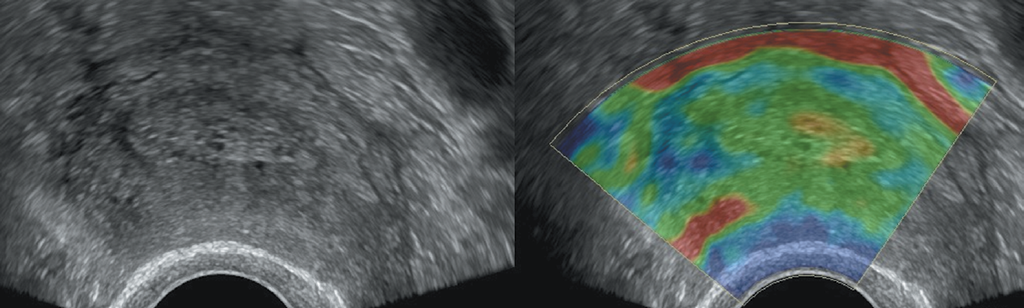

Помимо толщины эндометрия с помощью УЗИ необходимо оценить и отразить в протоколе исследования структуру, васкуляризацию, жесткость и наличие жидкости в полости матки. В случае тамоксифен-индуцированных изменений эндометрий аваскулярный, мягкий в режиме соноэластографии, жидкость в полости матки отсутствует (рис. 2). Из-за развития тамоксифен-индуцированной стромальной гиперплазии эндометрия корреляция между толщиной эндометрия и его патологическими изменениями у бессимптомных пациенток низкая, вследствие чего скрининговое вагинальное УЗИ и/или биопсия эндометрия не рекомендуются [25–27]. Перед началом терапии тамоксифеном целесоообразно выполнение трансвагинального УЗИ органов малого таза, так как пациентки с исходной патологией эндометрия имеют больший риск развития тамоксифен-индуцированного РЭ.

Рис. 2. Пациентка В. Постменопауза 5 лет. Прием тамоксифена — 3 года 8 месяцев. Толщина эндометрия — 10 мм. При ЦДК — эндометрий аваскулярный. При эластографии — второй (мягкий) тип эластичности. Кистозная атрофия эндометрия

Fig. 2. Patient V., 5 years postmenopausal, after 3 years 8 months of Tamoxifen therapy. Endometrial thickness = 10 mm. Endometrial tissue is avascular (colour Doppler imaging) and soft (elastography). Cystic endometrial atrophy